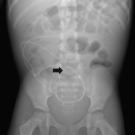

Danielle Young, MD; Courtney Miller, MD

While abdominal CSF pseudocyst is a rare complication of VP shunt placement, both proximal and distal shunt insufficiency should be considered in shunt-dependent children presenting with headache, nausea,...